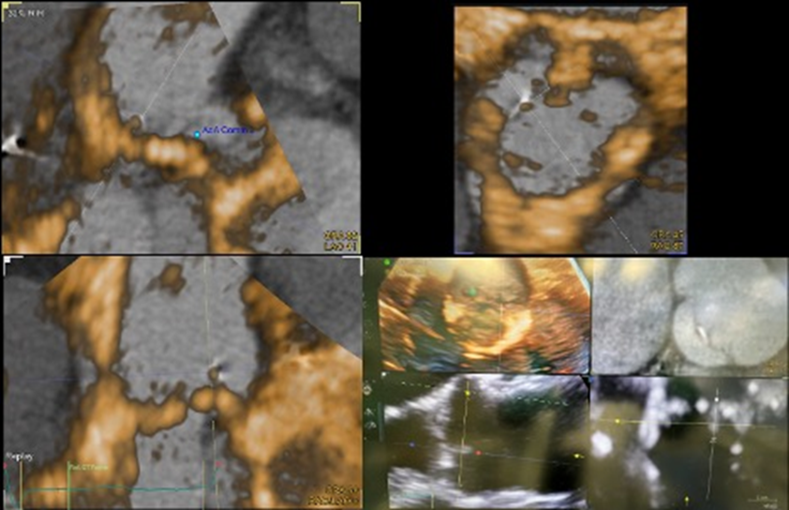

On the current presentation, the patient underwent repeat transthoracic echocardiography with bubble study and contrast-enhanced transthoracic echocardiography, neither of which demonstrated an intracardiac shunt or left ventricular thrombus. Electrocardiographically (ECG) synchronized cardiac computed tomography angiography (cCTA) was then performed as the final diagnostic test, supported by recent evidence demonstrating a higher diagnostic yield than echocardiography in the evaluation of acute stroke (Rinkel et al., 2022). cCTA revealed a 2-mm low-density tissue excrescence arising from the noncoronary cusp of the aortic valve (Figure 1) and simultaneously confirmed the absence of intracardiac thrombus or patent foramen ovale. Guided by cCTA localization, a repeat TEE with three-dimensional (3D) multiplanar reconstruction (Figure 2) successfully visualized the lesion. Intraoperative four-dimensional (4D) TEE with CT fusion—an innovative multimodality integration not previously described for this indication—was subsequently used for precise leaflet localization (Figures 3 and 4). Surgical pathology (Figure 5) demonstrated fibrocalcific degenerative changes of the noncoronary cusp and a small papillary fibroelastoma (PFE), which was deemed the most likely source of the patient’s recurrent cerebrovascular events.

Figure-3

Figure-4